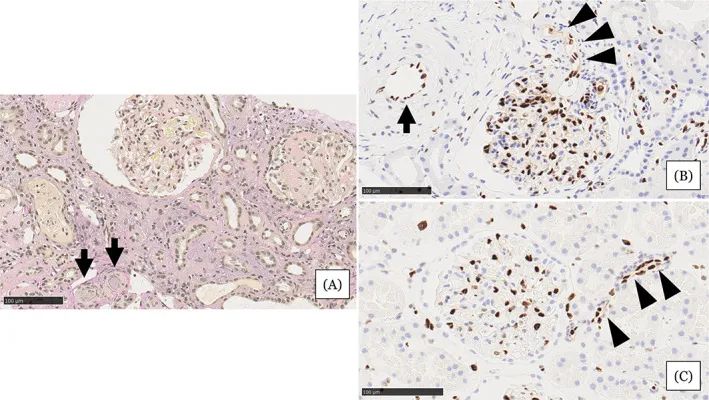

圖注:在住院第31天進(jìn)行的腎活檢結(jié)果。A,顯示小動(dòng)脈被粘液性?xún)?nèi)膜增厚(箭頭)堵塞,腎小球萎縮,毛細(xì)血管壁起皺,嚴(yán)重的間質(zhì)單核細(xì)胞浸潤(rùn)伴腎小管損傷。B,EC細(xì)胞核的缺乏在小動(dòng)脈(箭頭)中很突出。在相鄰的小動(dòng)脈(箭頭)中注意到不同大小的不規(guī)則細(xì)胞核。C,EC的等距核在血壓正常的腎臟供體的腎臟小動(dòng)脈中形成有序的線。比例尺 =100μm